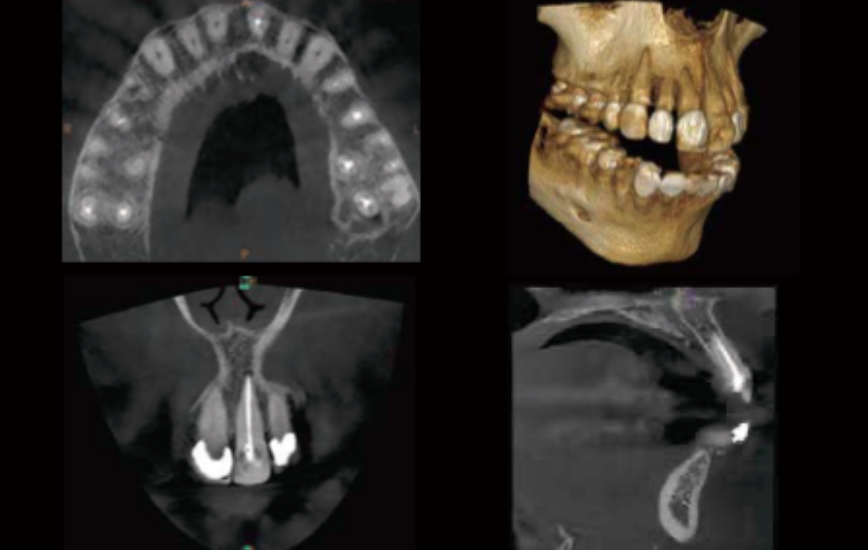

正確・的確な診療を行うための低線量歯科用CT、高度な感染対策を考えた滅菌機器から、3D口腔内スキャナーでの歯の型取りやマウスピース矯正、各チェアーに配置した口腔内カメラによる治療前後の比較など、患者様の負担の軽減と、治療の正確性を考えたを環境をご提供いたします。